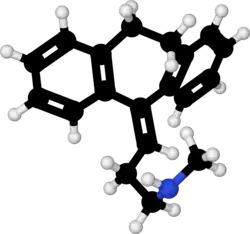

| Formula | C19H21N |

Nortriptyline is an active metabolite of amitriptyline by demethylation in the liver. Chemically, it is a secondary amine dibenzocycloheptene and pharmacologically it is classed as a first-generation antidepressant.[36]

Nortriptyline is a tricyclic compound, specifically a dibenzocycloheptadiene, and possesses three rings fused together with a side chain attached in its chemical structure.[43] Other dibenzocycloheptadiene tricyclic antidepressants include amitriptyline (N-methylnortriptyline), protriptyline, and butriptyline.[43][44] Nortriptyline is a secondary amine tricyclic antidepressant, with its N-methylated parent amitriptyline being a tertiary amine.[45][46] Other secondary amine tricyclic antidepressants include desipramine and protriptyline.[47][48] The chemical name of nortriptyline is 3-(10,11-dihydro-5H-dibenzo[a,d]cyclohepten-5-ylidene)-N-methyl-1-propanamine and its free base form has a chemical formula of C19H21N1 with a molecular weight of 263.384 g/mol.[49] The drug is used commercially mostly as the hydrochloride salt; the free base form is used rarely.[49][50] The CAS Registry Number of the free base is 72-69-5 and of the hydrochloride is 894-71-3.[49][50][51]